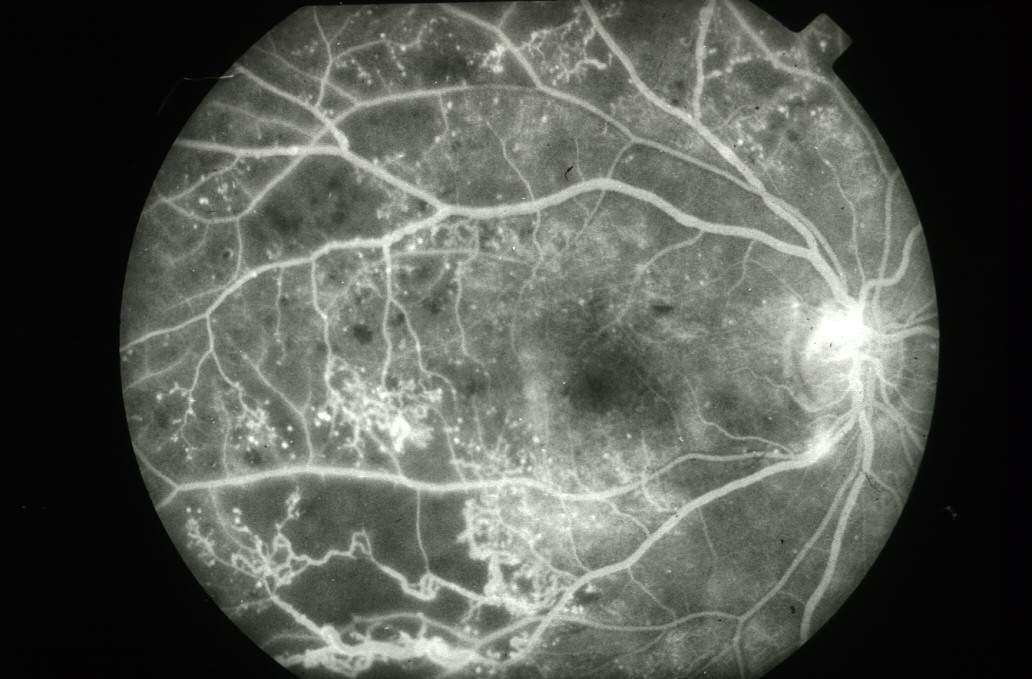

眼底筛查的主要方法是用眼底镜(简便易行)或眼底照相(客观记录)检查。免散瞳眼底照相更适宜糖尿病患者的初筛和无糖尿病视网膜病变患者的定期检查,可在糖尿病专科进行。对于糖尿病视网膜病变Ⅲ期以上的患者,可进一步请眼科医师行眼底荧光血管造影和OCT(光学相干断层扫描)检查,以指导治疗。

Ⅰ~Ⅲ期病变较轻,对视力影响不大,称为非增殖性病变。当视网膜病变发展到新生血管形成(Ⅳ期)和纤维组织增生(Ⅴ期),以致发展到视网膜脱离统称为增殖性糖尿病性视网膜病变(PDR),最终导致失明,是成年人致盲的主要原因。

Ⅳ期:眼底有新生血管生成并发玻璃体出血,视力下降明显。

Ⅴ期:眼底有新生血管生成和纤维组织增生,视力和视野都有明显影响。

Ⅵ期:发生视网膜脱离,视力严重受损,甚至失明。